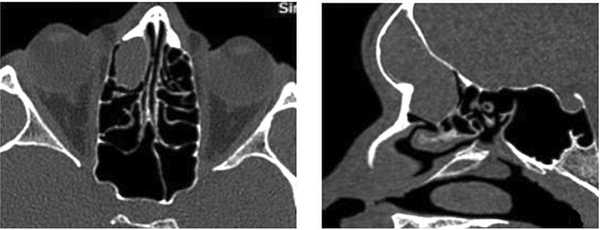

(Слева) При аксиальной КТ в костном окне определяется экспансивное поражение вершины пирамиды (ВП) справа с отсутствием ячеек, в норме заполненных газом, и трабекул. Дифференциально-диагноаический ряд: врожденная холестеатома, холестериновая гранулема, мукоцеле.

(Справа) При аксиальной МРТ Т1 ВИ у этого же пациента определяется распространенное мукоцеле ВП с интенсивноаью сигнала минимально более высокой, чем у ЦСЖ. Обратите внимание на гипоинтенсивный сигнал (ЦСЖ) во внутреннем слуховом канале сразу же за мукоцеле. Низкоинтенсивный сигнал на Т1 ВИ исключает холестериновую гранулему.

(Слева) При аксиальной МРТ Т2 ВИ определяется равномерно гиперинтенсивный сигнал в мукоцеле ВП. На ДВИ (не показано) не обнаружено ограничения диффузии. Экспансивное поражение ВП с гипо- (Т1) и гипер- (Т2) интенсивным сигналом и без ограничения диффузии крайне подозрительно на мукоцеле.

(Справа) При аксиальной МРТ Т2 у другого пациента определяется гиперинтенсивный сигнал (Т2) в экспансивном мукоцеле ВП. Сигнал Т1 гипоинтенсивный (не холестериновая гранулема), ограничение диффузии отсутствует (не врожденная холестеатома).